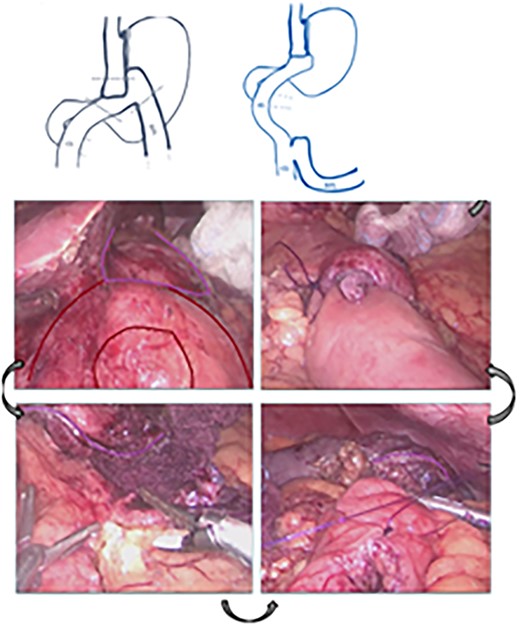

A 29-year-old woman originally from Ecuador’s Amazon region who presented with a history of grade II obesity (body mass index of 37) had undergone bariatric surgery (OAGB) 30 days before admission to our hospital. The patient showed intolerance to a liquid diet and symptoms of reflux starting at the immediate postoperative period, in addition to repeated bilious vomiting after progression to a semisolid diet. Physical examination showed normal vital signs, the abdomen was tender without signs of peritoneal irritation. The protein profile showed alterations with evidence of malnutrition. Abdominal Computed Tomography showed evidence of efferent intestinal loop bending with decreased passage of enteric contrast (Fig. 1A and B). An endoscopy showed stenosis of the gastroenteric anastomosis and obstruction of the efferent loop (Fig. 2).

(A) Computed Tomography: Afferent loop bending and gastroenteric anastomotic stenosis. (B) Radiograph showing distal efferent obstruction.

The patient was referred for laparoscopic revision surgery with conversion to RYGB (Fig. 3). In the postoperative period, a torpid evolution included vomiting on various occasions, as well as the detection of ascaris on one occasion. A new upper GI endoscopy showed evidence of permeable gastrojejunal anastomosis and acute inflammatory changes (Fig. 4), and the patient received antiparasitic treatment. Because of persistent symptoms of obstruction, a new surgical intervention was performed, which showed the presence of ascaris in the entero-enteric anastomosis causing its obstruction (Fig. 5). A new anastomosis was performed at a distance of 30 cm from the obstruction (Fig. 6). After the patient showed improvement and tolerated a liquid diet, she received treatment for ascaris and was discharged with good evolution.